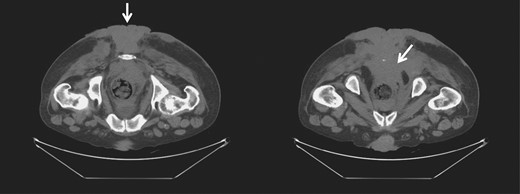

However, ~6 weeks later, he was readmitted due to regrowth of the invasive anal condyloma. All of the areas previously quiescent and clean of tumor were full of new lesions, extending into the pelvic sidewall and the anorectal region, as well as the area of excision. The lesions deteriorated with necrosis, foul odor, and abscesses over time, and debridement and drainage were performed mostly to manage the wound and reduce septic risk (Fig. 4). Multiple readmissions for secondary infections and peri-lesion abscesses occurred for months.

Gross image (A) and CT of the pelvis and perineum (B) showing tumor recurrence.